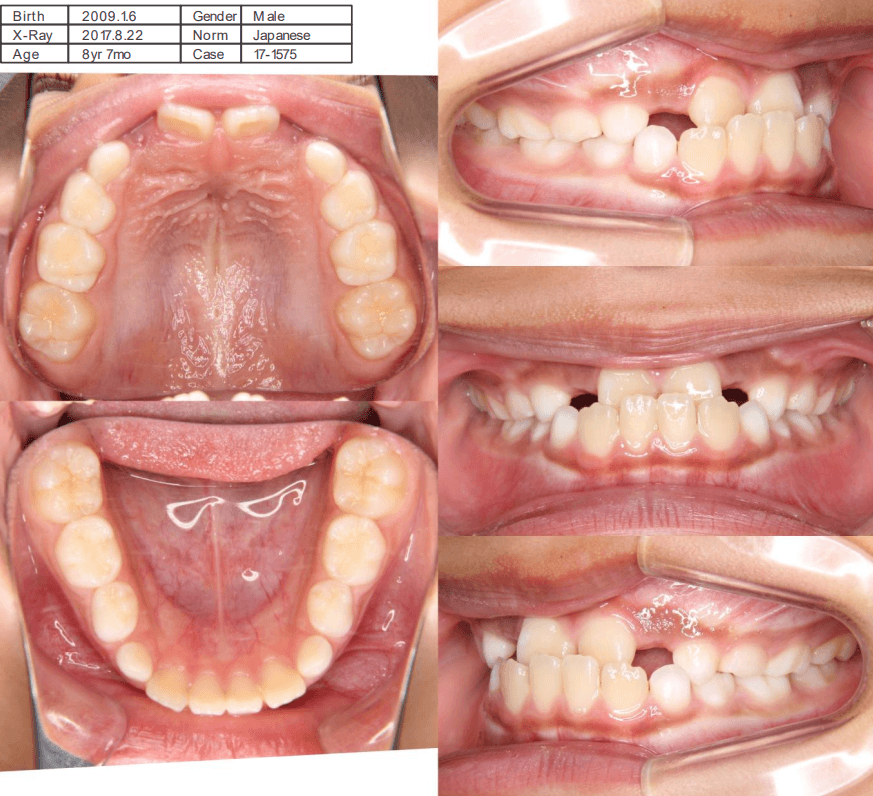

| 年齢・性別 | 8歳7ヶ月の男児 |

|---|---|

| 主訴 | 前歯がうまく噛み合わず、食事時に違和感があるとのことで来院されました。保護者様からは、将来的な歯並びの不安についてもご相談がありました。 |

| 治療期間・回数 | 1年3ヶ月・11回 |

| 費用 | 400,000円(税別) |